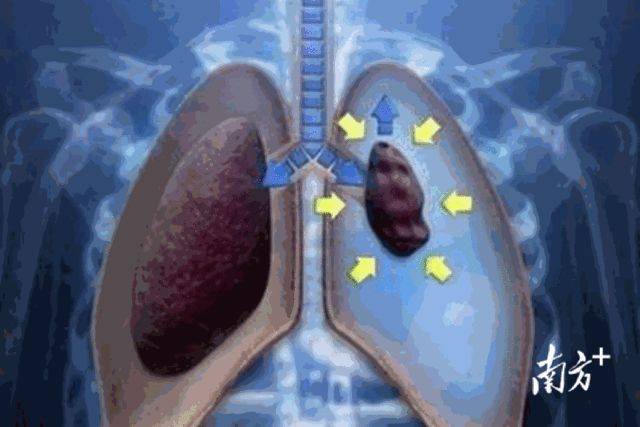

气胸示意图:胸腔气体进入 , 肺被压缩变小未经培训的针灸意外频发针灸危险性须知晓事实上 , 因为私自扎针引发断针、晕针、血肿、扎伤器官甚至感染的意外有许多 。 2019年 , 广医三院急诊科就曾救治过一名突发胸痛的老伯 。 老伯送来医院时面容痛苦 , 大汗淋漓 , 血氧下降 , 双侧呼吸音较低 。 检查胸片后 , 医院发现导致老伯气胸的原因 , 也是在家自行针灸 。 原来 , 老伯的妻子退休后自学成才 , 一直给全家人针灸保健强身 。 老伯在一次体检中发现肺纹理增粗后 , 妻子每天在他后背针灸 , 希望达到祛除肺病之功效 。 但这一次 , 针灸意外扎破了肺泡 , 导致老伯双侧气胸 , 危及生命 。 好在 , 广医三院医生为他进行了胸腔闭式引流 , 他最终有惊无险 , 转危为安 。 针灸是国家级非物质文化遗产 。 它是通过经络、腧穴的传导作用 , 以及应用一定的操作法 , 来刺激穴位 , 起到营卫气血、温通经脉的作用 。 虽有效果 , 但未经过正规医疗培训的针灸行为 , 实则十分危险 。 比如 , 因体位或针刺手法不当等 , 会导致病人针刺过程中出现头晕目眩、恶心欲吐 , 冷汗出 , 四肢厥冷 , 甚至神志昏迷等现象;未经严格消毒、重复使用的针 , 则可致深部软组织感染与破伤风 。 而凝血功能障碍患者、皮肤有感染或破损处、糖尿病患者、婴幼儿、孕妇、经期女性等身体情况较特殊的患者 , 不适合或慎用针灸 。 广医三院中医科主任、中医师胥海斌提醒 , 一支针看上去普通寻常 , 实际却暗藏风险 。 针灸等有创医疗行为一定要到正规医疗场所进行 , 切记不要凭借经验和所谓的教程自行摸索 。 截至7月16日24时 , 全省累计报告新冠肺炎确诊病例2796例(境外输入1230例) 。 目前 来源:广东健康头条(采访人员:陈伊纯)责编:岑婉梅